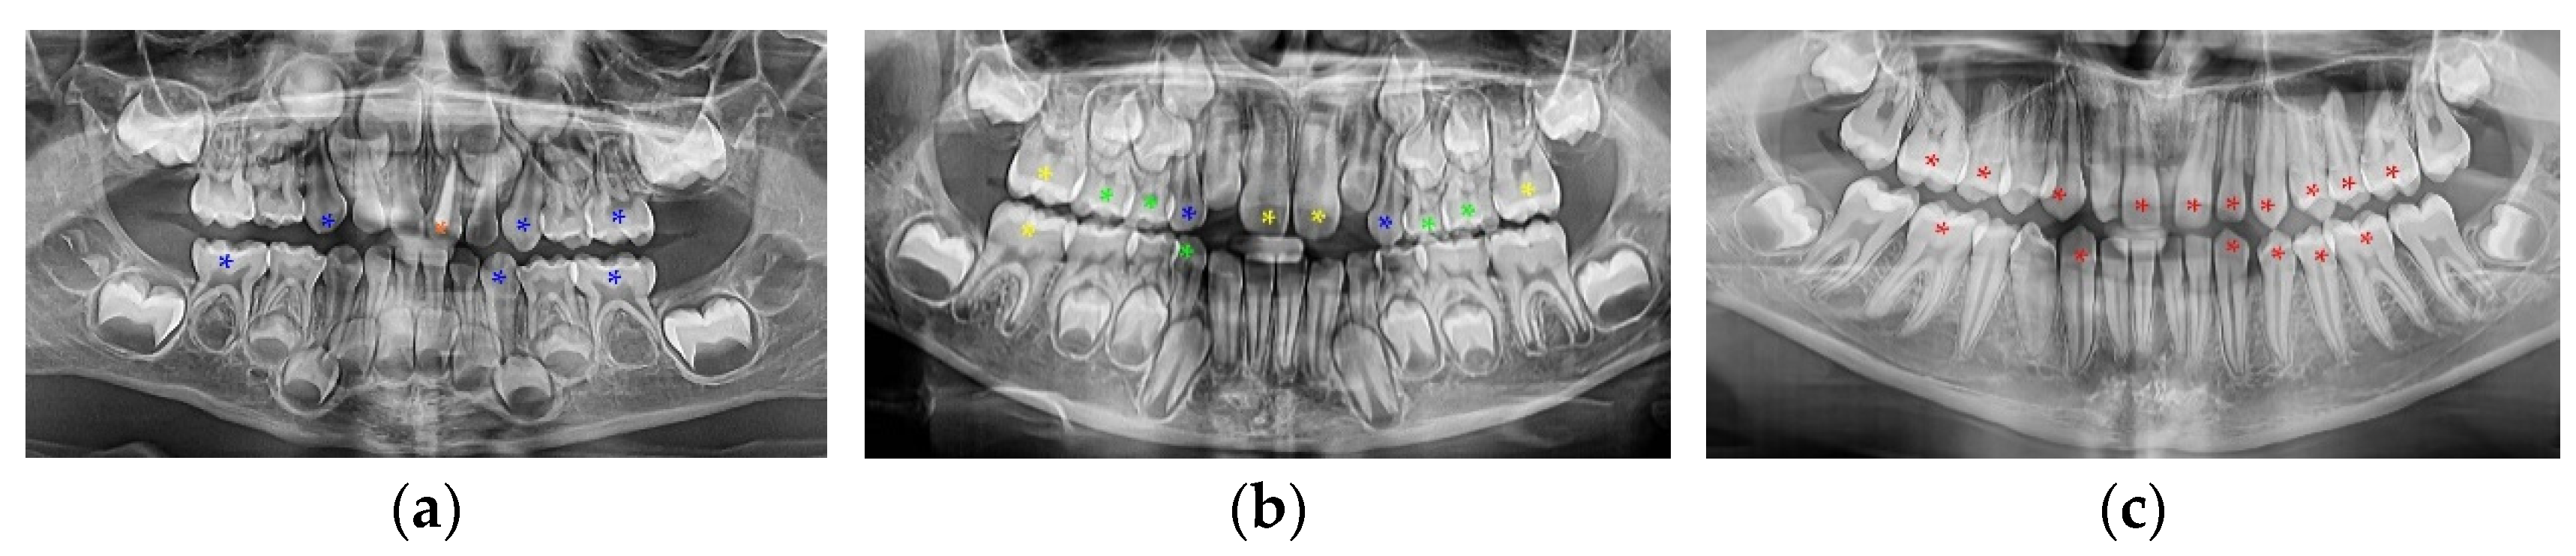

2. Materials and Methods